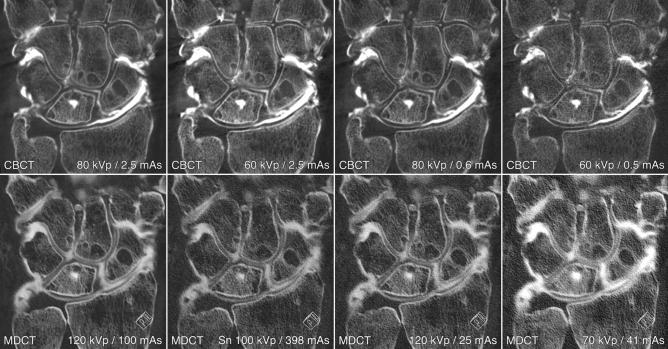

Modern cone-beam CT systems are capable of ultra-high-resolution 3D imaging in addition to conventional radiography and fluoroscopy. The combination of various imaging functions in a multi-use setup is particularly appealing for musculoskeletal interventions, such as CBCT arthrography (CBCTA). With this study, we aimed to investigate the feasibility of CBCTA of the wrist in a "one-stop-shop" approach with a gantry-free twin robotic scanner that does not require repositioning of subjects. Additionally, the image quality of CBCTA was compared to subsequent arthrograms on a high-end multidetector CT (MDCTA). Fourteen cadaveric wrists received CBCTA with four acquisition protocols. Specimens were then transferred to the CT suite for additional MDCTA. Dose indices ranged between 14.3 mGy (120 kVp/100 effective mAs; full-dose) and 1.0 mGy (70 kVp/41 effective mAs; ultra-low-dose) for MDCTA and between 17.4 mGy (80 kVp/2.5 mAs per pulse; full-dose) and 1.2 mGy (60 kVp/0.5 mAs per pulse; ultra-low-dose) for CBCTA. Subjective image quality assessment for bone, cartilage and ligamentous tissue was performed by seven radiologists. The interrater reliability was assessed by calculation of the intraclass correlation coefficient (ICC) based on a two-way random effects model. Overall image quality of most CBCTA was deemed suitable for diagnostic use in contrast to a considerable amount of non-diagnostic MDCTA examinations (38.8%). The depiction of bone, cartilage and ligaments in MDCTA with any form of dose reduction was inferior to any CBCTA scan with at least 0.6 mAs per pulse (all p < 0.001). Full-dose MDCTA and low-dose CBCTA were of equal quality for bone tissue visualization (p = 0.326), whereas CBCTA allowed for better depiction of ligaments and cartilage (both p < 0.001), despite merely one third of radiation exposure (MDCTA-14.3 mGy vs. CBCTA-4.5 mGy). Moderate to good interrater reliability was ascertained for the assessment all tissues (ICC 0.689-0.756). Overall median examination time for CBCTA was 5.4 min (4.8-7.2 min). This work demonstrates that substantial dose reduction can be achieved in CT arthrography of the wrist while maintaining diagnostic image quality by employing the cone-beam CT mode of a twin robotic X-ray system. The ability of the multi-use X-ray system to switch between fluoroscopy mode and 3D imaging allows for "one-stop-shop" CBCTA in minimal examination time without the need for repositioning.

现代锥形束 CT 系统除了常规射线照相和透视外,还能够进行超高分辨率的 3D 成像。在多用途设置中组合各种成像功能对于肌肉骨骼介入特别有吸引力,例如锥形束 CT 关节造影术(CBCTA)。通过这项研究,我们旨在研究一种无架式双机器人扫描仪的 CBCTA 的可行性,该扫描仪不需要重新定位受试者即可进行腕关节的“一站式”成像。此外,还比较了 CBCTA 的图像质量与后续在高端多排 CT(MDCTA)上的关节造影术。14 个尸体手腕接受了四种采集方案的 CBCTA。然后将标本转移到 CT 套件中以进行额外的 MDCTA。剂量指数范围为 MDCTA 的 14.3 mGy(120 kVp/100 有效 mAs;全剂量)和 1.0 mGy(70 kVp/41 有效 mAs;超低剂量)以及 CBCTA 的 17.4 mGy(80 kVp/2.5 mAs 每脉冲;全剂量)和 1.2 mGy(60 kVp/0.5 mAs 每脉冲;超低剂量)。七位放射科医生对骨骼、软骨和韧带组织的主观图像质量进行了评估。通过计算基于双向随机效应模型的组内相关系数(ICC)来评估组内可靠性。与相当数量的非诊断性 MDCTA 检查(38.8%)相比,大多数 CBCTA 的总体图像质量被认为适合诊断使用。任何形式的剂量减少的 MDCTA 中骨骼、软骨和韧带的显示均不如任何至少有 0.6 mAs 每脉冲的 CBCTA 扫描(均 p < 0.001)。全剂量 MDCTA 和低剂量 CBCTA 对骨骼组织可视化的质量相同(p = 0.326),而 CBCTA 允许更好地显示韧带和软骨(均 p < 0.001),尽管仅为 MDCTA 的三分之一辐射暴露(MDCTA-14.3 mGy 与 CBCTA-4.5 mGy)。对于所有组织的评估,均获得了中等至良好的组内可靠性(ICC 0.689-0.756)。CBCTA 的总体中位数检查时间为 5.4 分钟(4.8-7.2 分钟)。这项工作表明,通过使用双机器人 X 射线系统的锥形束 CT 模式,可以在腕关节 CT 关节造影术中实现大量剂量减少,同时保持诊断图像质量。多用途 X 射线系统在透视模式和 3D 成像之间切换的能力允许在最短的检查时间内进行“一站式”CBCTA,而无需重新定位。